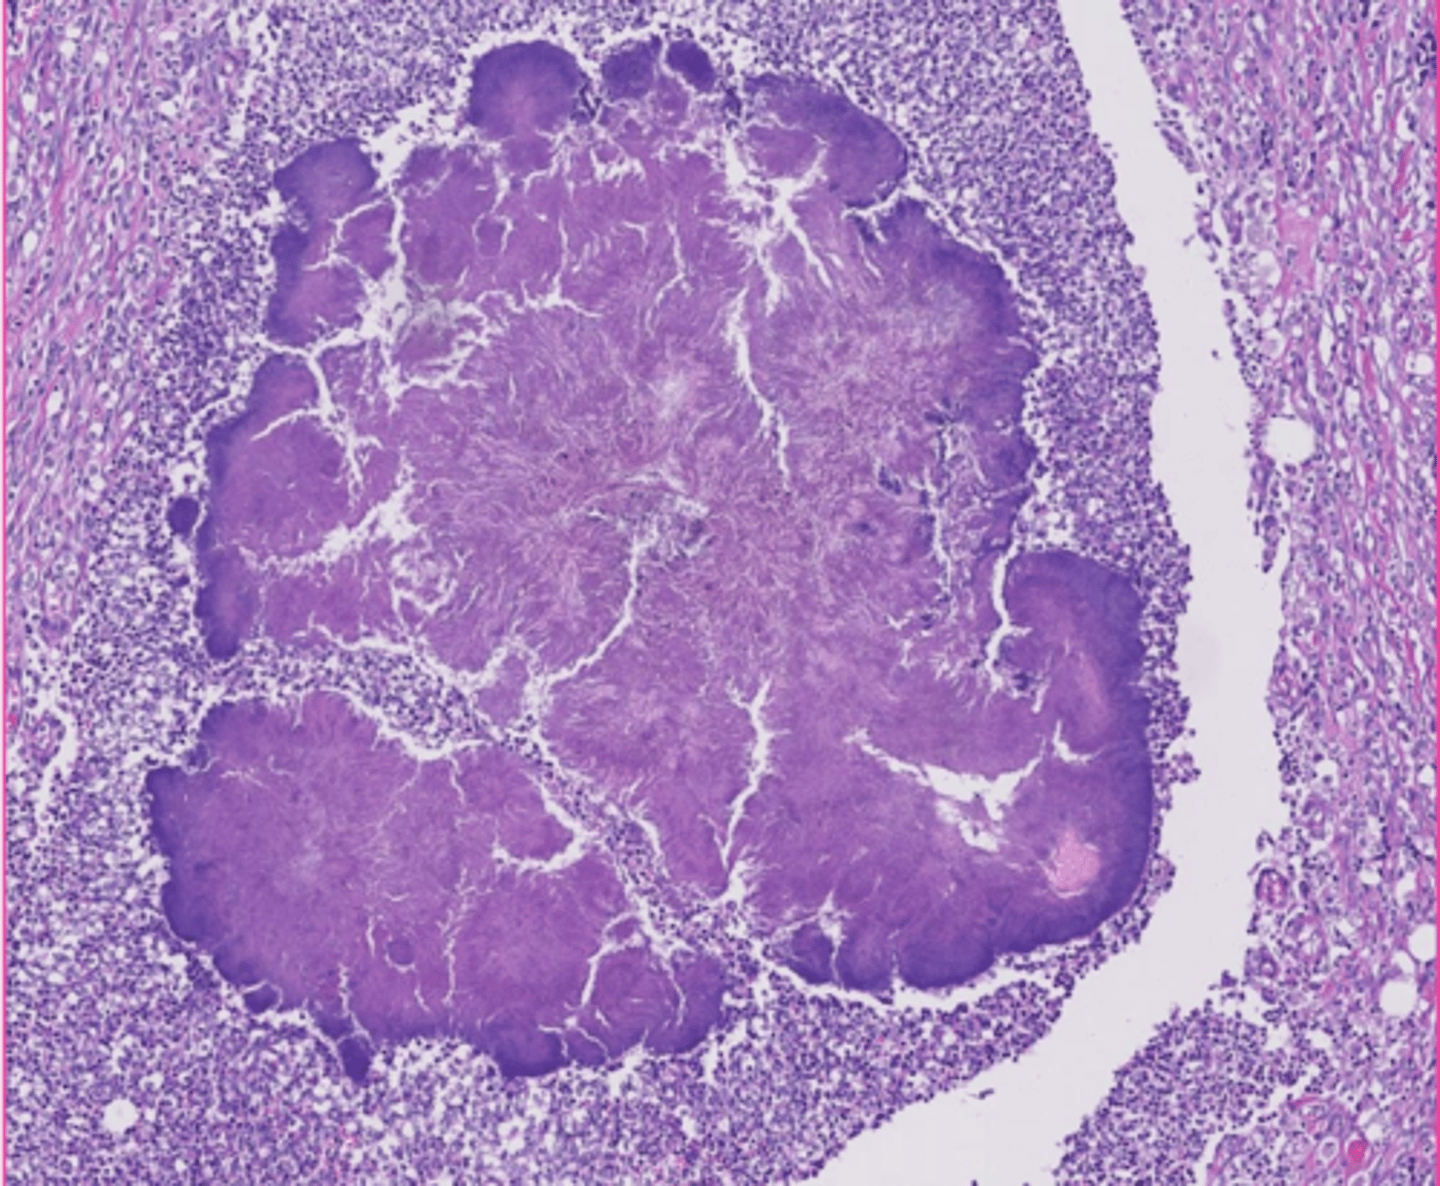

amyloid

describe the extracellular accumulation